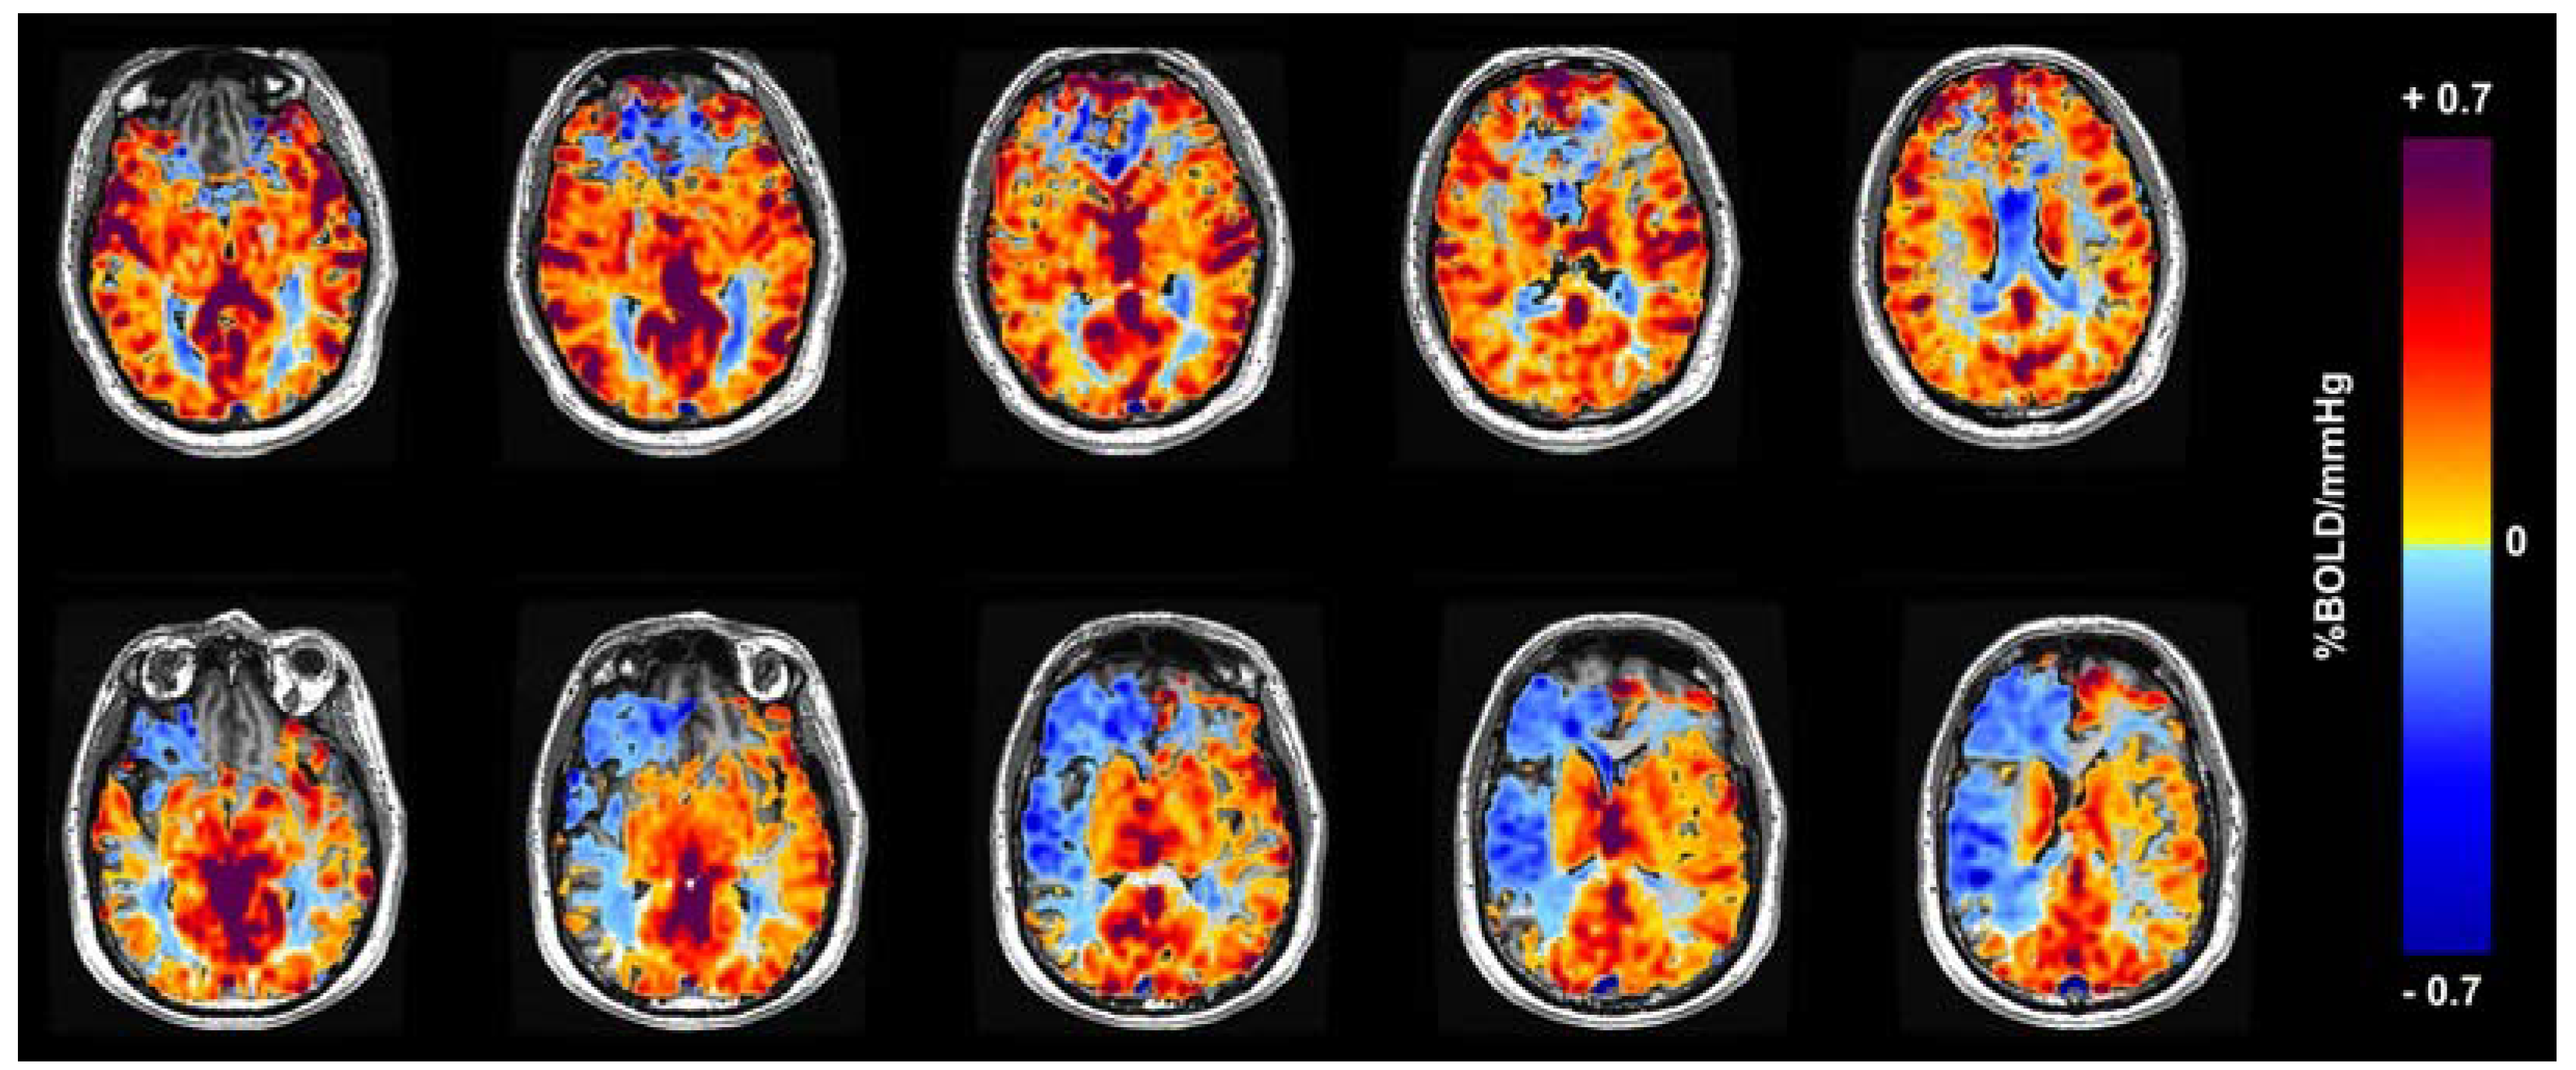

1.1. CVR: Clinical Workflow